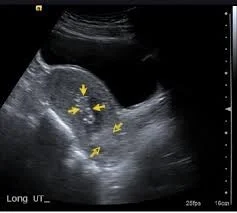

- U/S and Doppler study.